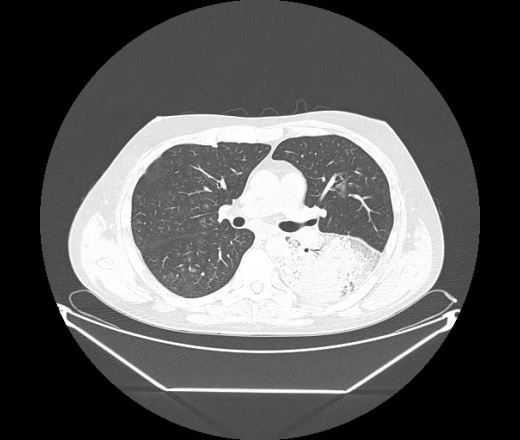

М. 1984 г.р.  Лихорадка 39, кашель , одышка.. и надоевший всем вопрос- "типично ли для ковид?" ( в настоящее время на него обязательно нужно дать ответ в своем протоколе)

На мой взгляд нетипично для ковид: много центрально-расположенных поражений, лобарное поражение нижней доли слева. 50/50

Не типичая картина для ковид.

КТ-признаки двусторонней бактериальной пневмонии.

Все верно, здесь абсолютно нетипичная картина, несмотря на матовое стекло с ретикулярными изменениями, но почему-то  посчитали иначе. Кстати,  "малыша" не заметили)?